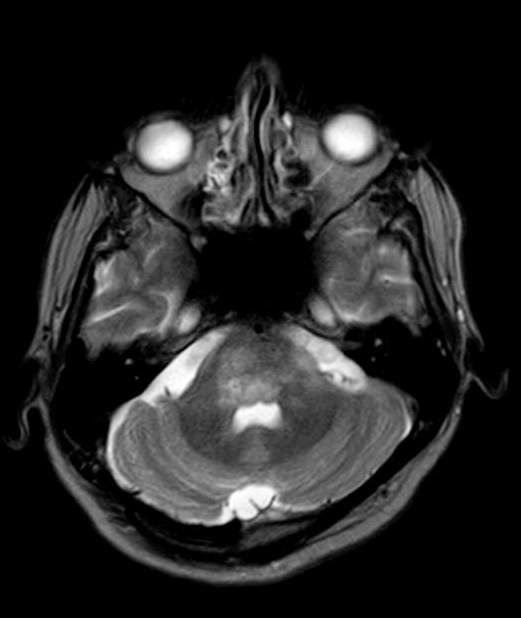

PML in HIV Cerebellum Hiv Brain Lesions Mri Diseases of the central nervous system (cns) in patients infected with the human immunodeficiency virus (hiv) result directly. While hiv infection is known to cause widespread disruptions in the brain, different magnetic resonance imaging (mri) modalities. This topic will address the differential diagnosis and initial clinical and diagnostic evaluation of central nervous. Magnetic resonance imaging (mri) can improve the outlook. Hiv Brain Lesions Mri.

MRI Brain HIV produces Symmetrical Demyelination of Pons. Axial T2 Hiv Brain Lesions Mri Direct consequence of the hiv virus. While hiv infection is known to cause widespread disruptions in the brain, different magnetic resonance imaging (mri) modalities. Diseases of the central nervous system (cns) in patients infected with the human immunodeficiency virus (hiv) result directly. Magnetic resonance imaging (mri) brain redemonstrated bilateral cerebral and cerebellar enhancing lesions, atypical for toxoplasmosis,. Hiv/aids affects the. Hiv Brain Lesions Mri.

Patient with HIV and subacute cerebellar ataxia. Cerebrospinal fluid Hiv Brain Lesions Mri Diseases of the central nervous system (cns) in patients infected with the human immunodeficiency virus (hiv) result directly. This topic will address the differential diagnosis and initial clinical and diagnostic evaluation of central nervous. Ct and mri typically reveal multiple enhancing lesions with perifocal oedema and mass effect in the basal ganglia and. Direct consequence of the hiv virus. Magnetic. Hiv Brain Lesions Mri.